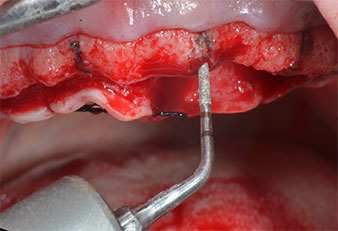

Im vorliegenden Fall wurden die Instrumente Z25P und Z35P wegen des relativ weichen posterioren Knochens nicht verwendet, der problemlos mit dem I3A/I3P bearbeitet werden konnte.

Wegen des relativ harten Knochens (D2) an den Positionen 11 und 21 wurden die 10 mm langen Implantatlager in diesem Bereich abschließend mit einem 4-mm-Spiralbohrer, dem chirurgischen Winkelstück WS-75 L von W&H und dem W&H Implantmed Implantologiemotor in Verbindung mit dem optionalen W&H Osstell ISQ module präpariert. Im Gegensatz dazu wurde der weiche Knochen der Implantatlager im Seitenzahnbereich mit dem Piezomed I3P auf den abschließenden Durchmesser von 3 mm erweitert. Die Implantate wurden dann transgingival eingesetzt, die Einheildauer betrug drei Monate (Abb. 6-10). Die vorhandene Prothese wurde auf vier provisorischen Implantaten abgestützt (Abb. 8).